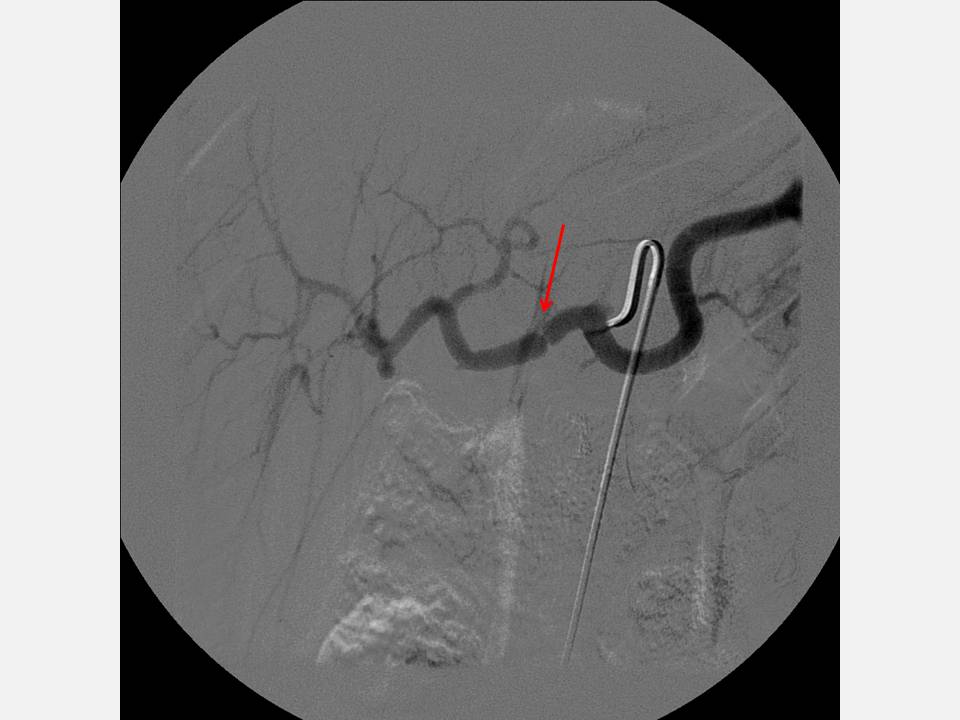

The Pump and the Tubes Hepatic Artery Complications Following Liver Transplant Arterial Conduit Liver Transplant although aortohepatic conduits (ahcs) provide an effective technique for arterialization in liver transplantation (lt). Arterial conduits (ac) in liver transplantation (lt) offer an effective rescue option when regular arterial graft revascularization is not. the use of an arterial conduit is an accepted alternative to the utilisation of native recipient hepatic artery for specific. the successful outcome in. Arterial Conduit Liver Transplant.

The Pump and the Tubes Hepatic Artery Complications Following Liver Transplant Arterial Conduit Liver Transplant although aortohepatic conduits (ahcs) provide an effective technique for arteriali‐zation in liver transplantation (lt). the successful outcome in orthotopic liver transplantation (olt) is critically dependent on the uncompromised hepatic graft blood. Arterial conduits (ac) in liver transplantation (lt) offer an effective rescue option when regular. although aortohepatic conduits (ahcs) provide an effective technique for arterialization in liver. Arterial Conduit Liver Transplant.

The Pump and the Tubes Hepatic Artery Complications Following Liver Transplant Arterial Conduit Liver Transplant Arterial conduits (ac) in liver transplantation (lt) offer an effective rescue option when regular arterial graft revascularization is not. Arterial conduits (ac) in liver transplantation (lt) offer an effective rescue option when regular. The successful outcome in orthotopic liver transplantation (olt) is critically dependent, among other. arterial conduits (ac) in liver transplantation (lt) offer an effective rescue option when. Arterial Conduit Liver Transplant.